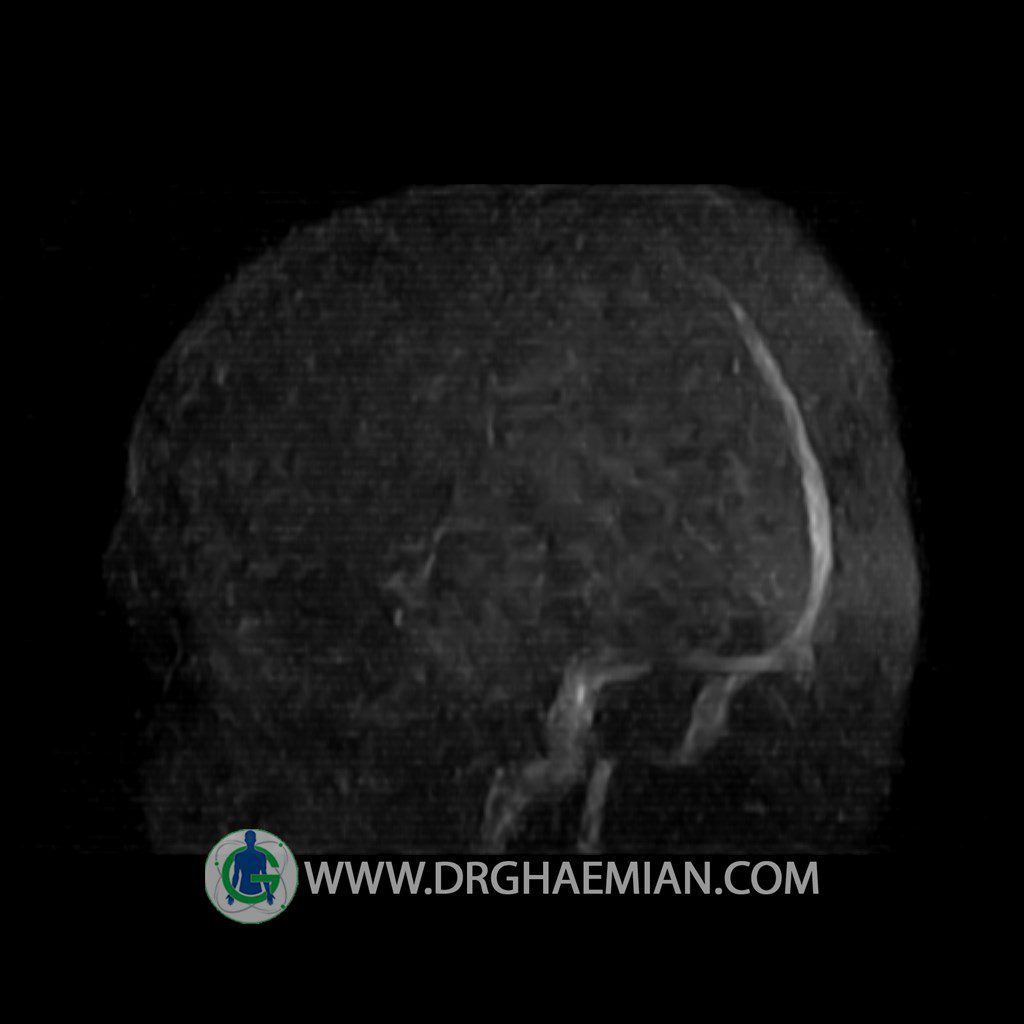

ام آر وی یک روش تصویربرداری دقیق و غیر تهاجمی است که برای معاینه ورید های بدن و ارزیابی سلامت رگ ها استفاده می شود. ورید ها خون را از اعضای بدن به قلب باز می گرداند تا دوباره اکسیژن و مواد مغذی به خون داده شود. ام آر وی جریان خون را ارزیابی و موارد غیرعادی مضر مانند لخته های خونی را شناسایی می کند. در این کیس ترومبوز دیواری مغز در سینوس عرضی راست و ترمبوز جزئی در سینوس عرضی چپ دیده می شود.

Technique: TOF ( time of flight ).

Images of the venous cranial vessels demonstrates a superior sagittal sinus of normal caliber with normal arrangement of draining superficial cerebral veins.

The great cerebral vein Galen inferior sagittal , straight sinus and left sigmoid sinus appear normal.

The right sigmoid sinus present a normal caliber.

The other evaluable deep cerebral veins , basal and labbe are normally developed and patent.

– Narrowing of left transverse sinus with filling defect & inthimal irregularity

suggestive for partial thrombosis

– Inthimal irregularity in anterior wall of right transverse sinus suggestive for mural thrombosis

are seen